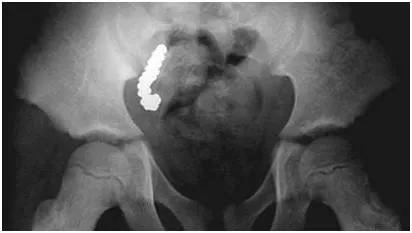

粪石,这个听起来有些陌生的名词,实际上是一种由未消化的食物残渣、纤维、种子等物质在消化道内长期积累形成的硬块。虽然它通常出现在胃部,但有时也会“跑”到阑尾中去,引发一系列健康问题。

粪石是如何进入阑尾的呢?这要从阑尾的结构说起。阑尾是一个细长的盲管,位于大肠的起始部位。当消化道中的物质通过盲肠时,一些不易消化的物质可能会进入阑尾腔。在正常情况下,这些物质会随着阑尾的蠕动被排出。然而,如果某些物质过于坚硬或体积较大,就可能在阑尾腔内积累,最终形成粪石。

粪石的存在对阑尾来说是一个不小的麻烦。它不仅会堵塞阑尾腔,还会导致阑尾黏膜充血水肿。更严重的是,粪石的压迫可能导致阑尾黏膜缺血坏死,继而引发感染。据统计,阑尾粪石坏疽穿孔的发生率高达18.5%,远高于非粪石引起的阑尾穿孔率(9.9%)。